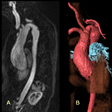

La dinámica de la corriente sanguínea a través de la válvula aórtica deformada y rígida provoca engrosamiento de las valvas y, posteriormente, calcificación. La obstrucción considerable desde el punto de vista hemodinámico provoca hipertrofia concéntrica de la pared ventricular izquierda. A menudo la aorta ascendente se dilata, lo que se denomina erróneamente dilatación “posestenótica”; la causa es una serie de anormalidades histológicas similares a las del síndrome de Marfan, que pueden originar disección aórtica.

Esta anomalía consiste en un estrechamiento difuso o localizado de la aorta ascendente, inmediatamente por encima del nivel de las arterias coronarias, en el borde superior de los senos de Valsalva. A diferencia de otras formas de estenosis aórtica, las arterias coronarias están sometidas a presiones sistólicas elevadas del ventrículo izquierdo, suelen dilatarse y volverse tortuosas y pueden sufrir ateroesclerosis prematura. En la mayoría de los pacientes hay un defecto genético localizado en la misma subunidad cromosómica de la elastina en el cromosoma 7.